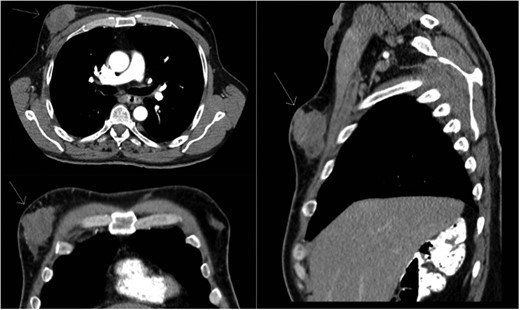

Staging positron emission tomography computed tomography (PET CT) was performed demonstrating activity in the right breast as well as mediastinal and hilar lymphadenopathy (Fig. 2). The patient underwent neoadjuvant chemotherapy and a repeat PET CT showed decreased activity in the right breast and no further lymphadenopathy (Fig. 3). A right modified radical mastectomy was performed. Pathologic examination revealed invasive ductal carcinoma, histologic grade III with closest margin at 1mm away. There was 0 out of 18 positive axillary lymph nodes. Pathologic staging was set at pT2N0M0, Stage IIA. Given the slim posterior margin, he received post mastectomy radiation therapy. Currently, the patient is receiving tamoxifen 20 mg once a day.

Preoperative staging CT scan. Chest wall mass noted to be 6.9 cm × 2 cm.